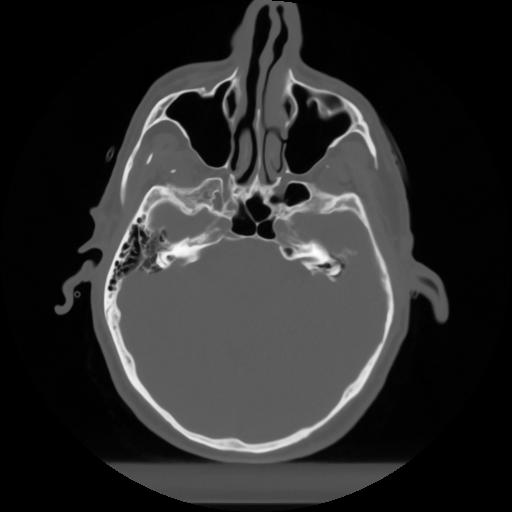

10 P.BLANDAS,,Axial,2.0,P.BLANDAS,,